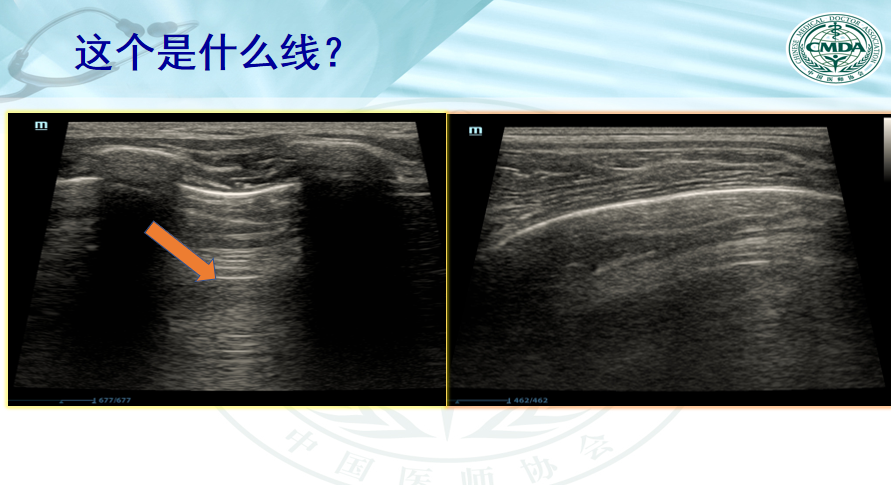

肺脏超声图像识别考核内容表,肺脏超声检查识图版,2024年4月12日(肺消融培训班)

肺脏超声图像识别考核内容表

肺脏超声检查考核版